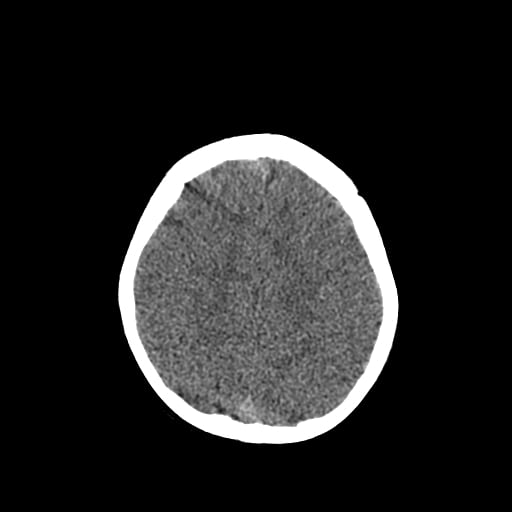

Age: 1

Sex: Male

Indication: Fall